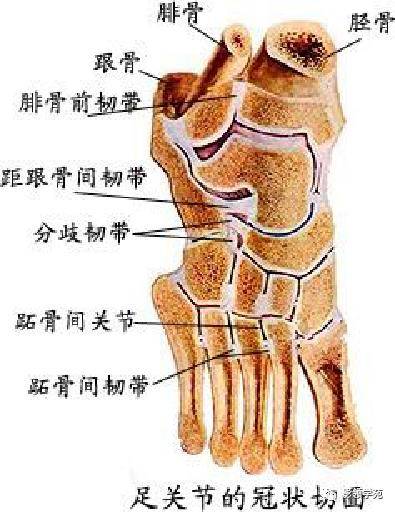

关节与韧带系统

关节与韧带系统